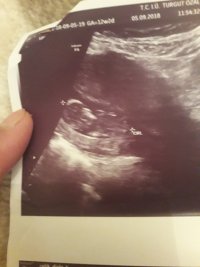

Nub teorisiyle cinsiyet tahmini bebeğim erkek mi kız mı ?

Banada yorum.yapin lutfen 12 haftaligiz

Nub teorsisi için cinsiyet tahmininde yorum isteyen arkadaşlar lütfen uyarımızı dikkate alın. Ultrason görüntüleri elinize ilk verildiği gibi net olmaz. Sık sık ışığa maruz kaldığı için görüntü kalitesi bozuluyor dolaysıyla bizlerde değerlendirme yapamıyoruz. Sizlere yorum yapabilmemiz için görüntü kalitesi aşağıdaki linkte yer alan görseller gibi olmalıdır. Ayrıca Bebeğin cinsiyeti net olarak 18-19-20. haftalarda belli olur..

Merhaba, yüklediğiniz görsellerde nub çıkıntısı anlaşılmıyor , dolaysıyla değerlendirme yapamıyoruz.. Görselin kalitesi aşağıdaki gibi olmaldır.. Sağlıklı gebelik süreci diliyorum.